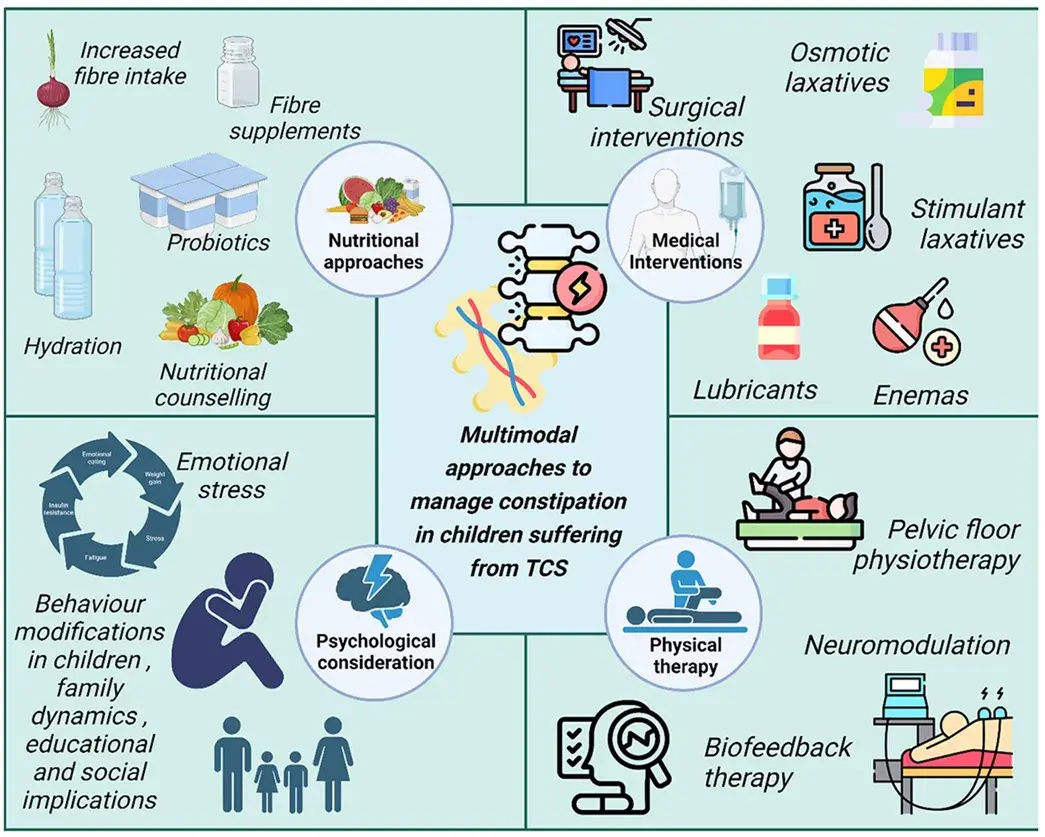

脊髓栓系综合征(TCS)早期发现困难,常常导致很多婴儿直至成年才被诊断出来。便秘是脊髓栓系患儿常见的术前症状和术后并发症,它经常被忽视,导致诊断延迟,对孩子的生活质量产生严重...